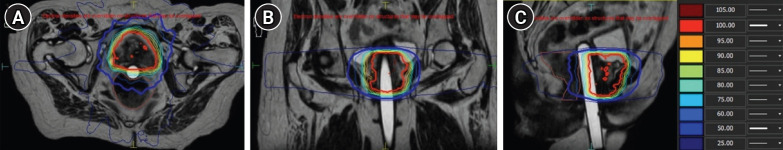

This study evaluates the use of magnetic resonance-guided radiation therapy (MRgRT) as an alternative to brachytherapy in treating para-urethral gynecological cancers, particularly for patients who are not candidates for brachytherapy. Five female patients with advanced para-urethral gynecological cancers underwent MRgRT using a custom 3-dimensional-printed intravaginal cylinder for image registration and treatment alignment. MRgRT was administered as a five-fraction adaptive boost following standard chemoradiation, with each fraction utilizing the cylinder to achieve precise positioning and improve organ sparing. A 1.5T magnetic resonance linear accelerator was used to deliver adapt-to-shape treatment, allowing real-time adjustments to compensate for anatomical variations. The cylinder served not only as a surrogate for accurate image registration but also as a spacer to displace the rectum from high-dose regions. The median follow-up period was 14.4 months, during which all patients completed treatment with no grade >3 genitourinary toxicities. Acute toxicities included dysuria and vaginal pain, while chronic toxicities, such as urinary incontinence and mild cystitis, were recorded in a subset of patients. Treatment achieved an overall survival rate of 100% and a recurrence-free survival rate of 80%. Dosimetric analysis demonstrated effective target coverage with minimal exposure to surrounding organs, particularly sparing the urethra from hotspots, unlike traditional brachytherapy. These results suggest that MRgRT with a vaginal cylinder offers a promising approach for managing para-urethral gynecological cancers in patients ineligible for brachytherapy. Further studies are warranted to validate these findings and refine treatment protocols.